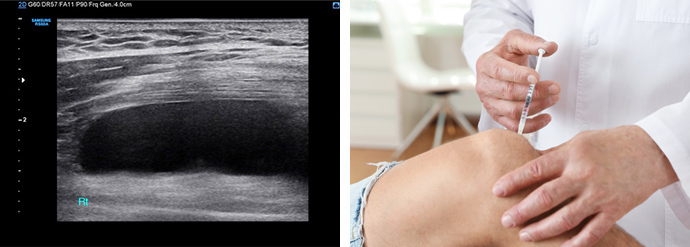

초음파 상 무릎 관절 내 물이 많이 차고 염증이 심한 상태(그림에서 까맣게 보이는 부분). 통풍 수치(요산수치)가 8.46으로 높아 통풍성 무릎 관절염 진단 하에 치료를 시작했습니다.

통풍 염증을 가라 앉히는 약은 효과를 1-2주 기다려야 하는데 그 동안 일상생활의 지장과 통증 때문에 관절강 내 염증과 통증을 감소시키는 스테로이드 주사 치료를 시행했습니다.